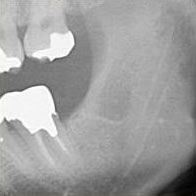

extractionImg007